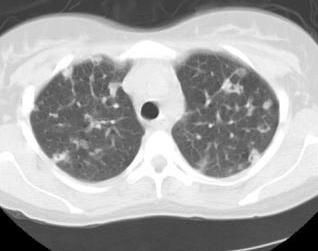

The patient was listless, diaphoretic, and appeared to be using accessory muscles of respiration. Temperature was 39°C (102.2°F); pulse, 120 beats/min; and blood pressure, 106/50 mm Hg. Examination of the chest revealed decreased air entry at bases. Heart sounds were normal without murmurs. Findings from the abdominal and neurologic examinations were normal, and there was no evidence of leg swelling. Hemoglobin concentration was 14.4 g/L, and white blood cell count was 19.3 x 109/L (polymorphonuclear leukocytes 77%, band forms 16%, eosinophils 4%, and monocytes 3%). Figures 1 and 2 show CT scans of the chest. Results of a lumbar puncture and a CT scan of the brain were unremarkable. Transesophageal echocardiography (TEE) found no cardiac vegetations. A culture taken from the catheter tip was positive for methicillin-sensitive Staphylococcusaureus.

Figure 2.

As seen in the Figures, CT scan of the chest found multiple subpleural peripheral nodules. Some lesions revealed cavitation, a finding consistent with septic pulmonary emboli (PE), given the confounding clinical findings of this patient.

The major findings on chest CT scan are multiple pulmonary peripheral nodules of varying size with evidence of cavitation.5 Mediastinal lymphadenopathy and/or peripheral wedge-shaped densities along the pleura and hilar are also possible.6 TEE is essential to rule out right-sided endocarditis as a source.